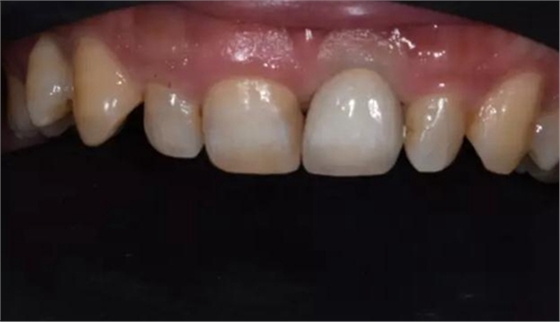

修復體試戴,修復體和原牙顏色上有輕微差異,不過患者本人非常滿意。

修復后正面口內(nèi)微笑照。